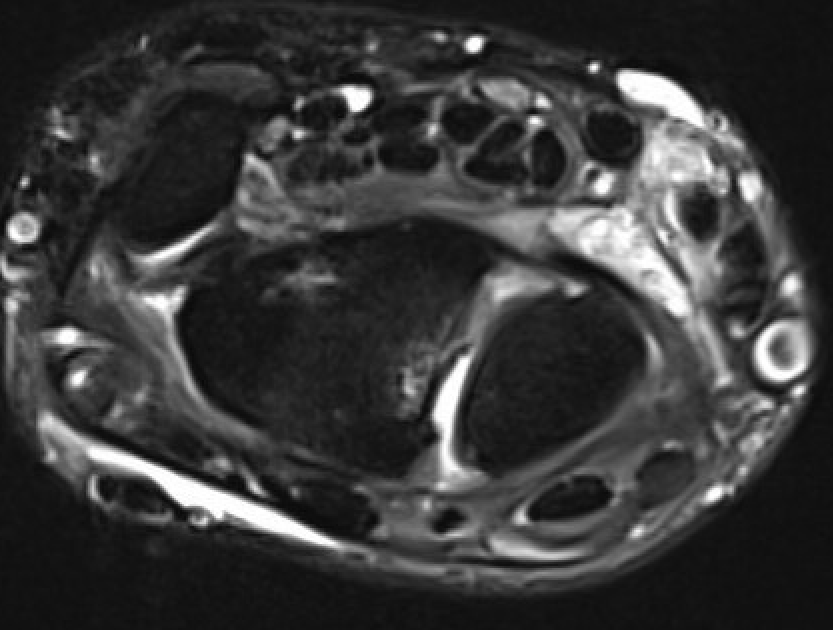

MRI

SL ligament injury with minimal disassociation / SL separation / dynamic instability

SL ligament injury with SL separation and static instability

Increased scapholunate angle